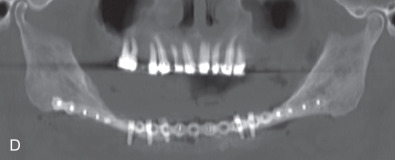

All of these systems allowed for convalescent function – life without MMF. RIF had the potential of dramatically shortening the course of treatment. However, its use was highly technique-sensitive with a steep learning curve. Thus, the incidence of complications increased dramatically due to operator error. Complications related to inadequate reduction – “the OIF” (open internal fixation … without the reduction) ( Figs. 1.16.1–1.16.3 ), inadequate fixation ( Figs. 1.16.4–1.16.7 ) and surgical misadventure ( Fig. 1.16.8 ) began to appear. Indeed, by the early 1990s operator error was the number one cause of mandibular fracture complications. Quite obviously, RIF is very unforgiving. When done poorly, one has a rigidly fixed mistake. The latest series of misadventures are related to the use of IMF screws. Bone-anchored arch bars will most likely be next. Not all believe that RIF and convalescent function is cost-effective with respect to the increased cost, potential for complications, and patient acceptance.